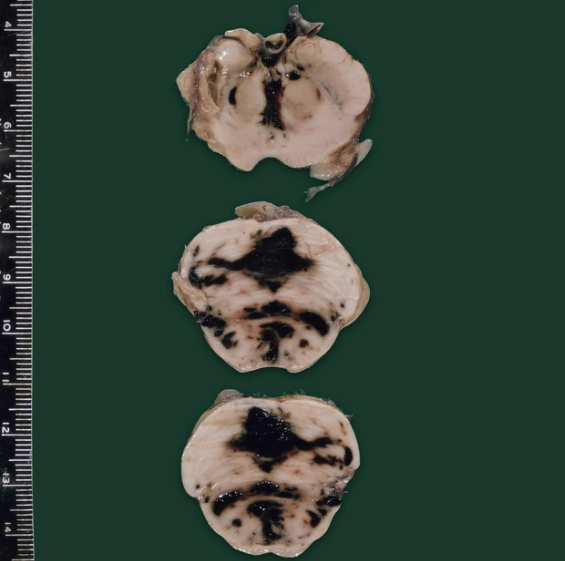

Bệnh não chấn thương mạn tính (Chronic Traumatic Encephalopathy - CTE)